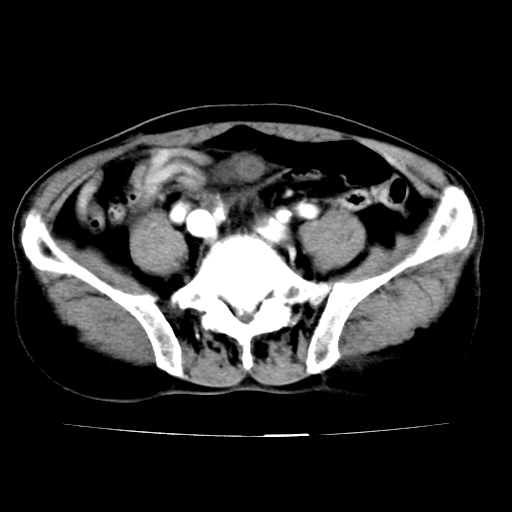

标题: V0243:右髂总动脉瘤附壁血栓形成?破裂?动静脉瘘? [打印本页]

标题: V0243:右髂总动脉瘤附壁血栓形成?破裂?动静脉瘘?

男,75岁,腹痛月余,彩超发现脐周腹主动脉异常回声。临床诊断:腹主动脉瘤。

ct诊断:右骼总动脉囊性动脉瘤并瘤内附壁血栓形成,与下腔静脉之间形成动静脉瘘。

请问各位老师:能排除动脉瘤破裂的可能吗?